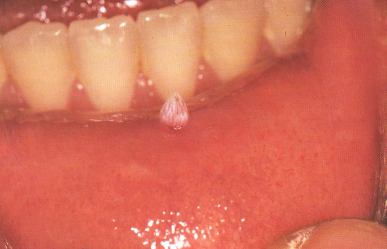

Fig. 3.18. Papiloma de la mucosa labial inferior.14

Clínicamente se observa como un crecimiento pedunculado, indoloro, firme, bien circunscrito con proyecciones características como dedos de guantes, que tienden a producir una superficie en forma de coliflor. Las lesiones son generalmente de color blanco, pero pudieran ser ligeramente rojas o del color de la mucosa normal según la cantidad de queratina presente.14 De base sésil o pediculada (Fig. 3.18). La mayoría de las lesiones son solitarias y se presentan comúnmente en el paladar blando, úvula, superficies ventral y dorsal de la lengua, encía y mucosa oral.3 El diagnóstico se hace clínicamente.14